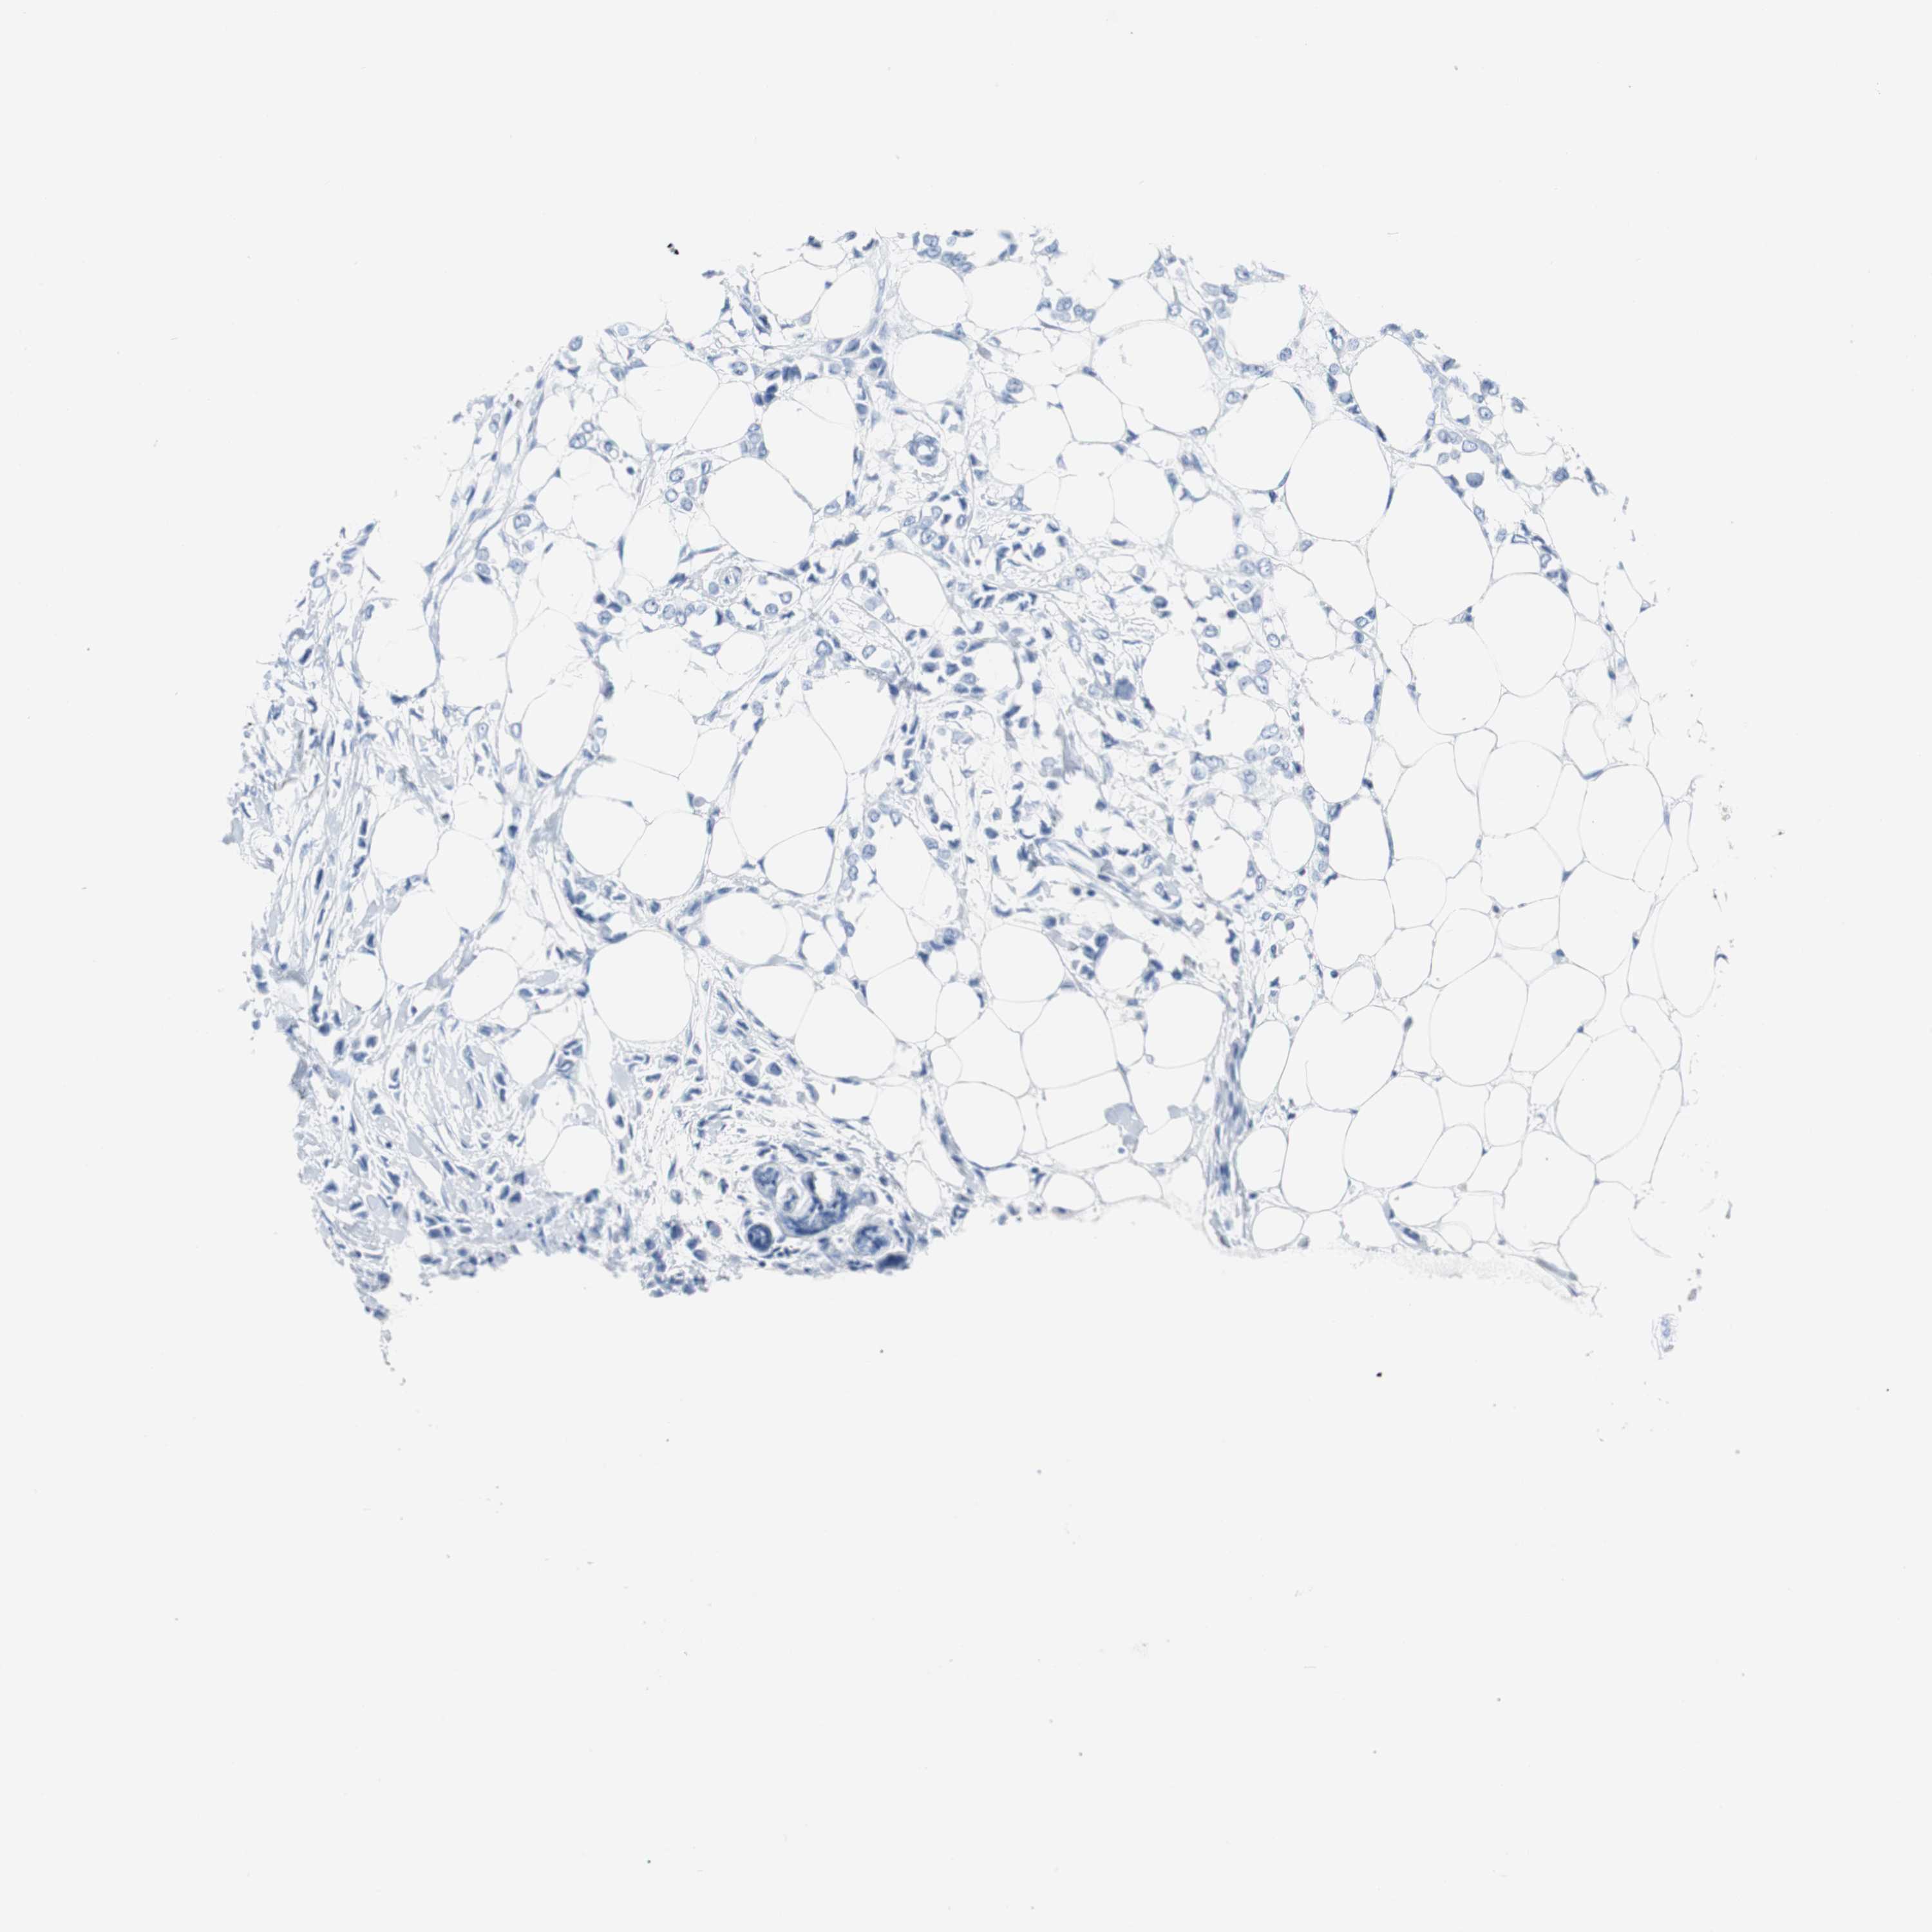

Breast cancer

Human cancer